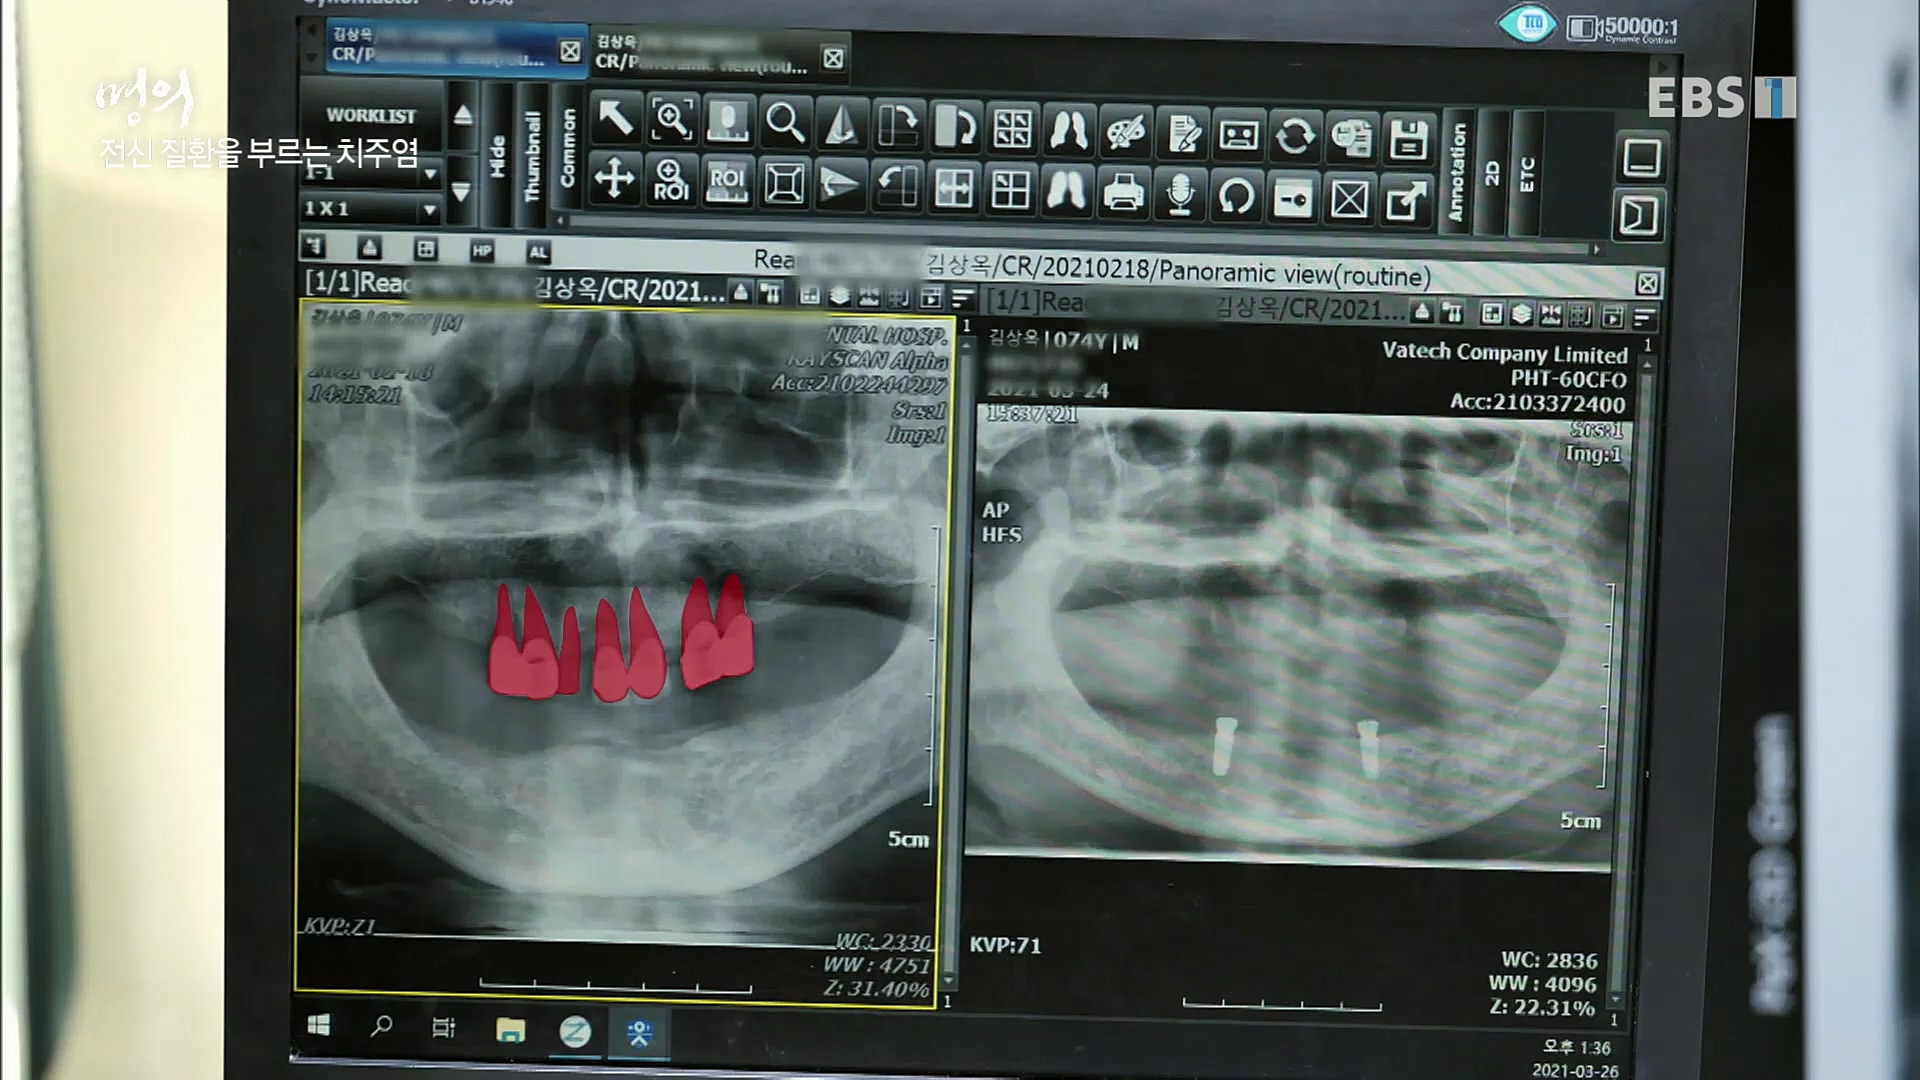

전신 건강을 위협하는 치주염

치주염이 코로나로 소홀해진 구강관리가 치아를 더 망가트리고 위험하게 만들며, 증상이 없기 때문에 특히 더 조심하고 치은염 단계에서 진행되지 않도록 예방해야한다